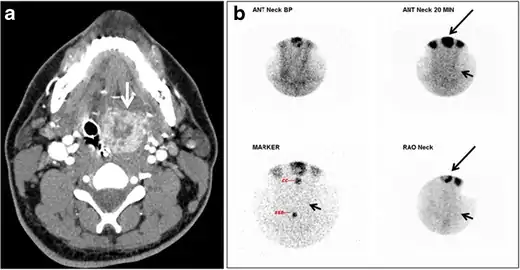

| CT scan and scintigraphy images of lingular ectopic thyroid | |

An ectopic thyroid, also called accessory thyroid gland, is a form of thyroid dysgenesis in which an entire or parts of the thyroid located in another part of the body than what is the usual case. A completely ectopic thyroid gland may be located anywhere along the path of the descent of the thyroid during its embryological development, although it is most commonly located at the base of the tongue, just posterior to the foramen cecum of the tongue. In this location, an aberrant or ectopic thyroid gland is known as a lingual thyroid.[3] If the thyroid fails to descend to even higher degree, then the resulting final resting point of the thyroid gland may be high in the neck, such as just below the hyoid bone.[3] Parts of ectopic thyroid tissue ("accessory thyroid tissue") can also occur, and arises from remnants of the thyroglossal duct, and may appear anywhere along its original length.[3] Accessory thyroid tissue may be functional, but is generally insufficient for normal function if the main thyroid gland is entirely removed.[3]